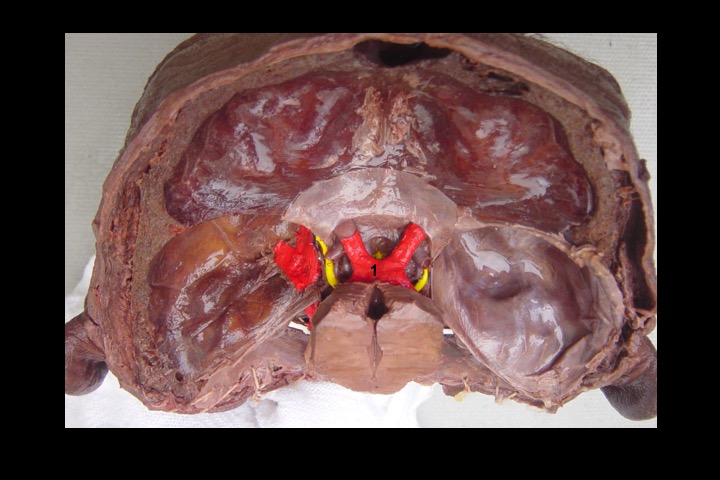

O Prof. Emérito da UFRJ Dr. Adalmir Morterá Dantas está disponibilizando através de nosso website e de nosso canal youtube (cursobom) o Museu de Neuroanatomia, no intuito de promover esta área de conhecimento junto aos estudantes de Medicina.

As figuras são apresentadas em 4 vídeos no youtube e podem ser obtidas via download clicando-se na figura em questão.